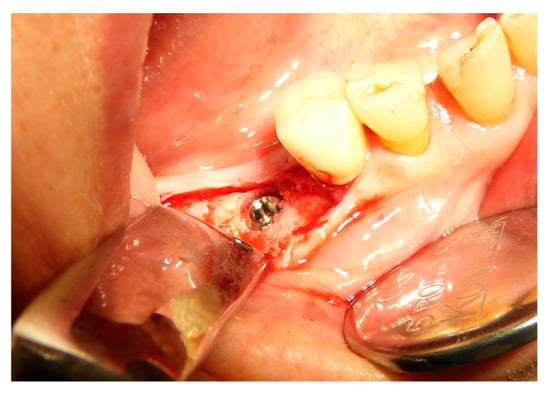

The vertical average defect was 9.16 mm, buccal lateral/palatal 7.0 mm, and mesio-distal 10.3 mm. The measurements were intraoperatively performed with a millimeter periodontal probe. The endodontic material mechanically cleaned before the tooth was placed inside the Tooth Transformer device. The endodontic material was removed using a drill bur with the attention to cut the canal in excess with the aim to remove all the cement. No surgical complications were registered. Pre and post-operative X-rays (section from CBCT) were collected from the same case (Figure 1, Figure 2, Figure 3 and Figure 4). After four months, 13 histological and histomorphometrical evaluations were performed (Figure 5). The Bone Volume/Total Volume average (BV%) was 41.47 (S.D. ± 11.51), the Residual Graft/Total Volume average (Graft%) was 16.60 (S.D. ± 7.09), and the Vital Bone/Total Bone average (VB%) was 21.89 (S.D. ± 9.72). No extraneous material (gutta-percha or cement) was detected in all samples (Table 3).

Figure 8. Ridge maintenance through the use of the extracted element and cover with a resorbable membrane.